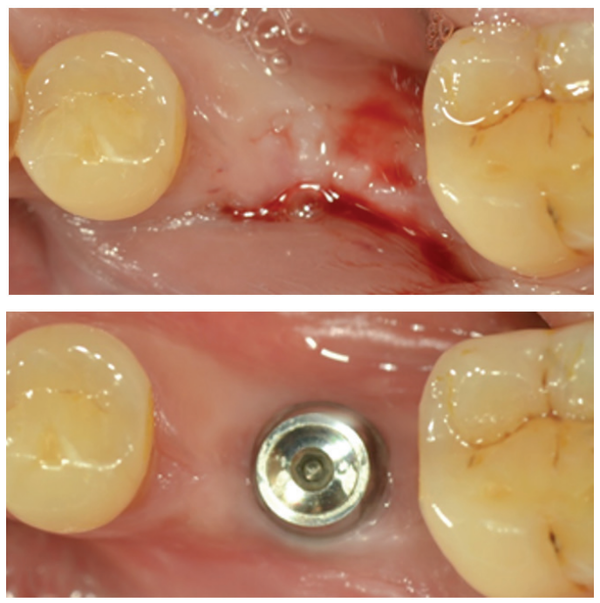

임상가들이 만나는 치조골이 항상 (그림 2-1, 上)과 같이 충분한 폭을 확보할 수 있는 경우라면 임플란트 수술의 난이도는 매우 낮아질 것이다. 하지만 환자의 치조골은 모든 경우가 다르고 (그림 2-2, 下)와 같이 충분한 골폭을 확보하기 힘든 경우도 빈번히 관찰된다.

이와 같이 골폭이 충분치 않은 경우 임상가들은 상방의 치조골을 삭제한 후에 임플란트 식립을 고려하거나 치조골의 concave한 부분에 GBR을 시행한 후 임플란트 식립을 계획한다.

두 방법 모두 가능하지만 그 과정에서 필연적으로 침습적 수술이 이뤄지고 치유 기간이 늘어나게 된다. 그러나 MagiCore는 독창적인 macro design과 그에 따른 최소침습적 수술 방법을 통해 [그림 2-2, 下]와 같이 상방의 잇몸 모양을 수정함과 동시에 불규칙한 뼈의 형태를 MagicCuff 부분으로 대체해 식립할 수 있다.

다만, 이러한 방법을 적용하여 임플란트를 식립하기 위해서는 수정된 gingiva line이 유지돼야 하며 Magic Cuff 일부분과 접촉하게 되는 치조골 부위가 증상이 없어야 한다는 조건을 충족시켜야 한다.

Bone level 2-piece 임플란트 시스템과는 달리 MagiCore 임플란트 시스템에서는 이러한 조건을 충족시키는 것이 어렵지 않다. (그림 3)